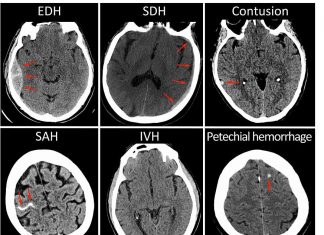

Research shows imaging after mild brain injury may predict outcomes

A new study published in JAMA Neurology suggests that certain features that appear on CT scans help predict outcomes following mild traumatic brain injury...